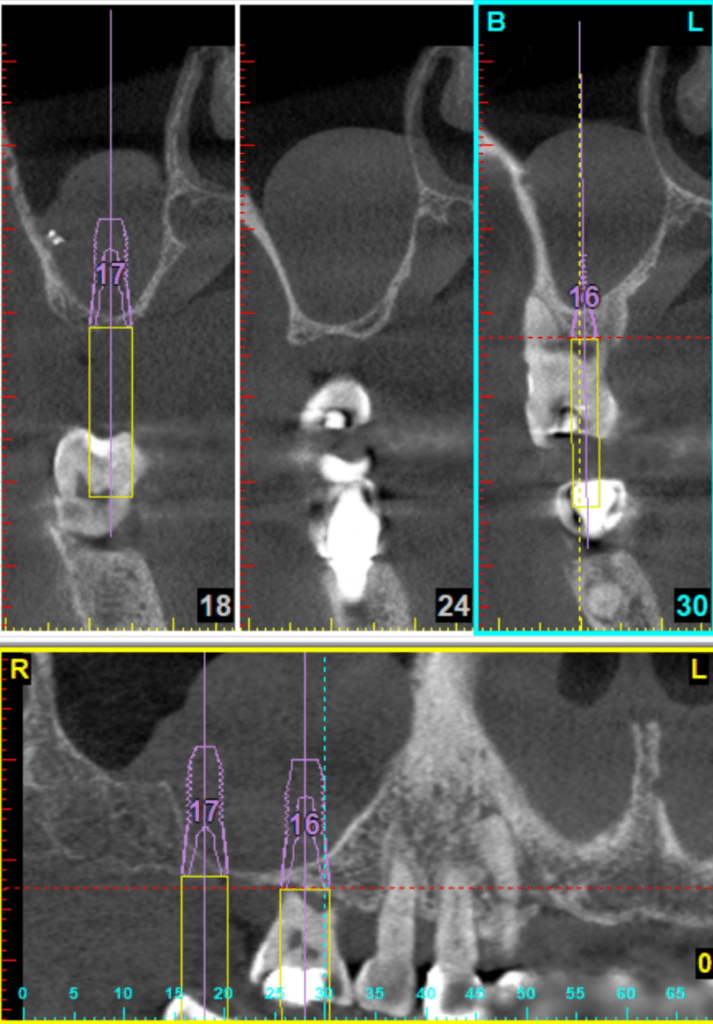

例如,一台開窗式鼻竇增高手術,能看好X光片與電腦斷層,腦中多次模擬手術過程,從切線設計、開窗位置、如何翻鼻竇膜、什麼位置有大血管、如何病人不在眼前,就可以先知道鼻竇內的高低起伏、器械需要準備哪些、有可能遇到什麼突發狀況、有什麼退路。這些都要想清楚。

十年來,我習慣每次開窗手術,都會親手繪製開窗所需要知道的刻度。骨頭高低起伏、牙根走向、血管位置、甚至有時候還會註記側窗骨質厚度等。當然也可以把電腦斷層的資料列印出來。

自己比較喜歡手繪,因為花個十分鐘,拿個鉛筆與橡皮擦,問自己一個問題:「什麼是最重要的資訊?」然後畫出最重要的幾個位置與刻度,相對位置與比例。透過親自手繪,比起列印斷層,來得更有臨場感,這也是手術前模擬的一環。

到手術當天,手繪圖就直接貼在旁邊,考試嘛,帶個小抄才不會答不出來啊~~

這也是我第一次嘗試在自然牙底下增高鼻竇,運氣不錯,自然牙底下的鼻竇質地平緩,只有顎側牙根稍有起伏,這也事先在3D模擬就知道,所以翻膜過程也不會感到驚訝與挫折。